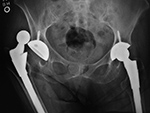

Bilateral total hip arthroplasty (THA) |

38 year old man with bilateral THA for advanced osteoarthritis. |

| Bilateral total hip arthroplasty (THA) |

| 38 year old man with bilateral THA for advanced osteoarthritis. The acetabular cup on an AP view of the pelvis should have 30-50 degrees of lateral inclination, which is measured as the angle between the rim of the acetabular cup and a line tangential to the ischial tuberosities. |

38 year old man with bilateral THA for advanced osteoarthritis. On a true cross-table lateral view of the hip there is normally 5-25 degrees of anteversion which is measured as the angle between the rim of the acetabular cup and a line drawn perpendicular to the horizontal surface. |

38 year old man with bilateral THA for advanced osteoarthritis. The distances from a line (C) between the centers of the femoral heads to a line running tangential to the ischial tuberosities (A) should be equal on each side, and the distances between the centers of the femoral heads to a line (B) running tangential to the tops of the greater trochanters should be equal on each side. Lines A, B, C should be parallel. |

38 year old man with bilateral THA for advanced osteoarthritis. The distances from the centers of the femoral heads on each side to the tops of the acetabular tear drops should be equal. |